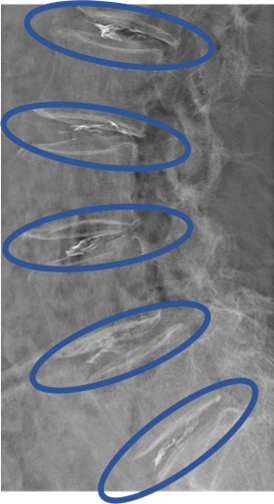

画像及び所見について

L1/2: 変性、膨隆、HIZ

L2/3: 変性、膨隆

L3/4: 変性、膨隆

L4/5: 変性、膨隆、両側椎間孔狭窄

L5/S: 変性、左ヘルニア

以上の事が画像上認められます。

L1/2、2/3、3/4、4/5、5/S に椎間板変性、椎間板ヘルニア、椎間孔狭窄 を認め、主症状の原因の可能性が高い。

DiscoGelを入れた後の画像になります。